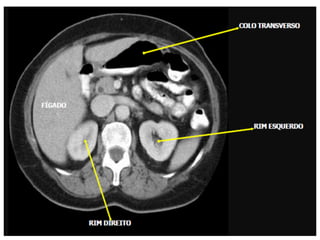

Varredura do abdome total

• Os limites são definidos pelo diafragma até

a sínfise púbica.